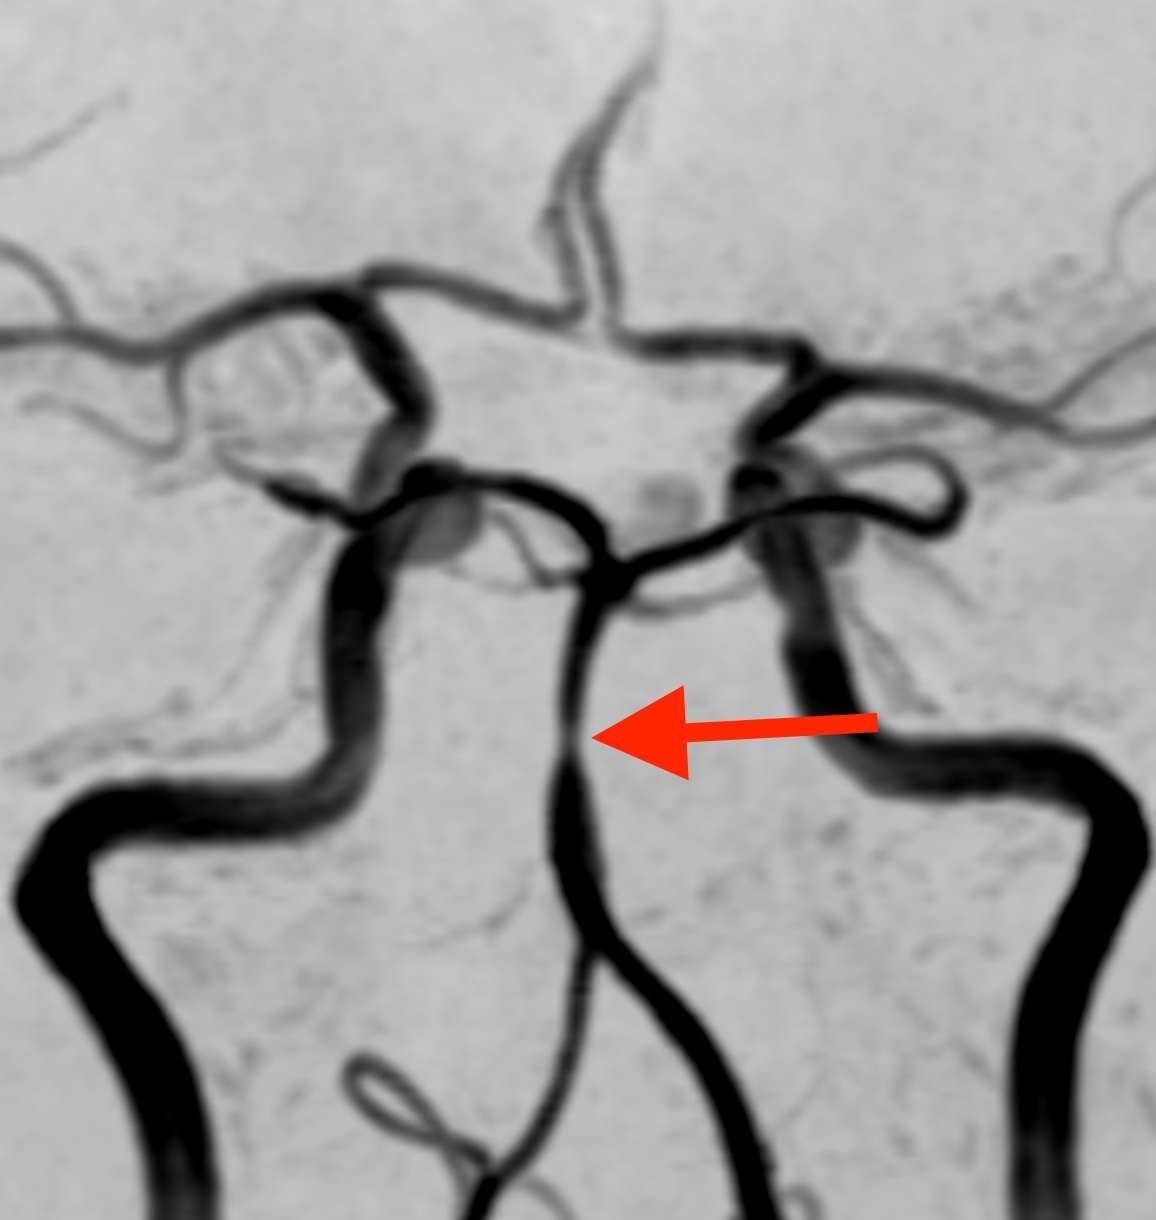

MRI検査で脳の血管を見たところ、

脳底動脈という血管の一部がくびれて細くなっており、その下の部分では、血管がソーセージのような形に膨らんでいます。そこで、この所見から可逆性脳血管攣縮症候群(RCVS)と診断しました。